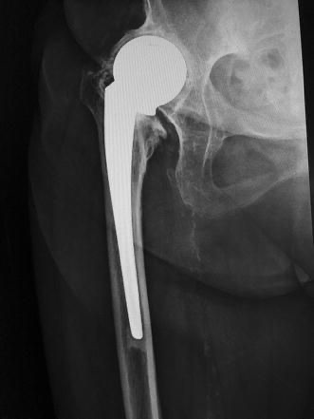

My job was initially predominantly orthopaedics, which I enjoyed as I had a pleasant and up-to-date boss, a New Zealander, John Addison. He had me doing the latest you-beaut procedure in no time – the Austin Moore prosthesis – for fractured necks of femurs.

McMurray osteotomy L and Austin Moore prosthesis R

John had developed his own technique for this and had his anaesthetist photograph the whole procedure on super-8 film so he could show it at orthopaedic meetings. The Charnley hip procedure was just coming into vogue and he was about to swing over but in the meantime he had me doing a McMurray osteotomy for osteoarthritis of the hip, a procedure which did not have a very long shelf life. It was designed to alter the weight-bearing of an OA hip and thereby relieve pain.

The policy on the unit for the numerous fractured hips we saw was to go directly to a replacement prosthesis for a subcapital fracture, rather than a Smith Peterson pin, which more often than not resulted in necrosis of the head of the femur, necessitating a second operation in a frail patient. I probably did 25 to 30 Austin Moores and that stood me in good stead at The Queen Elizabeth Hospital as a senior registrar later.